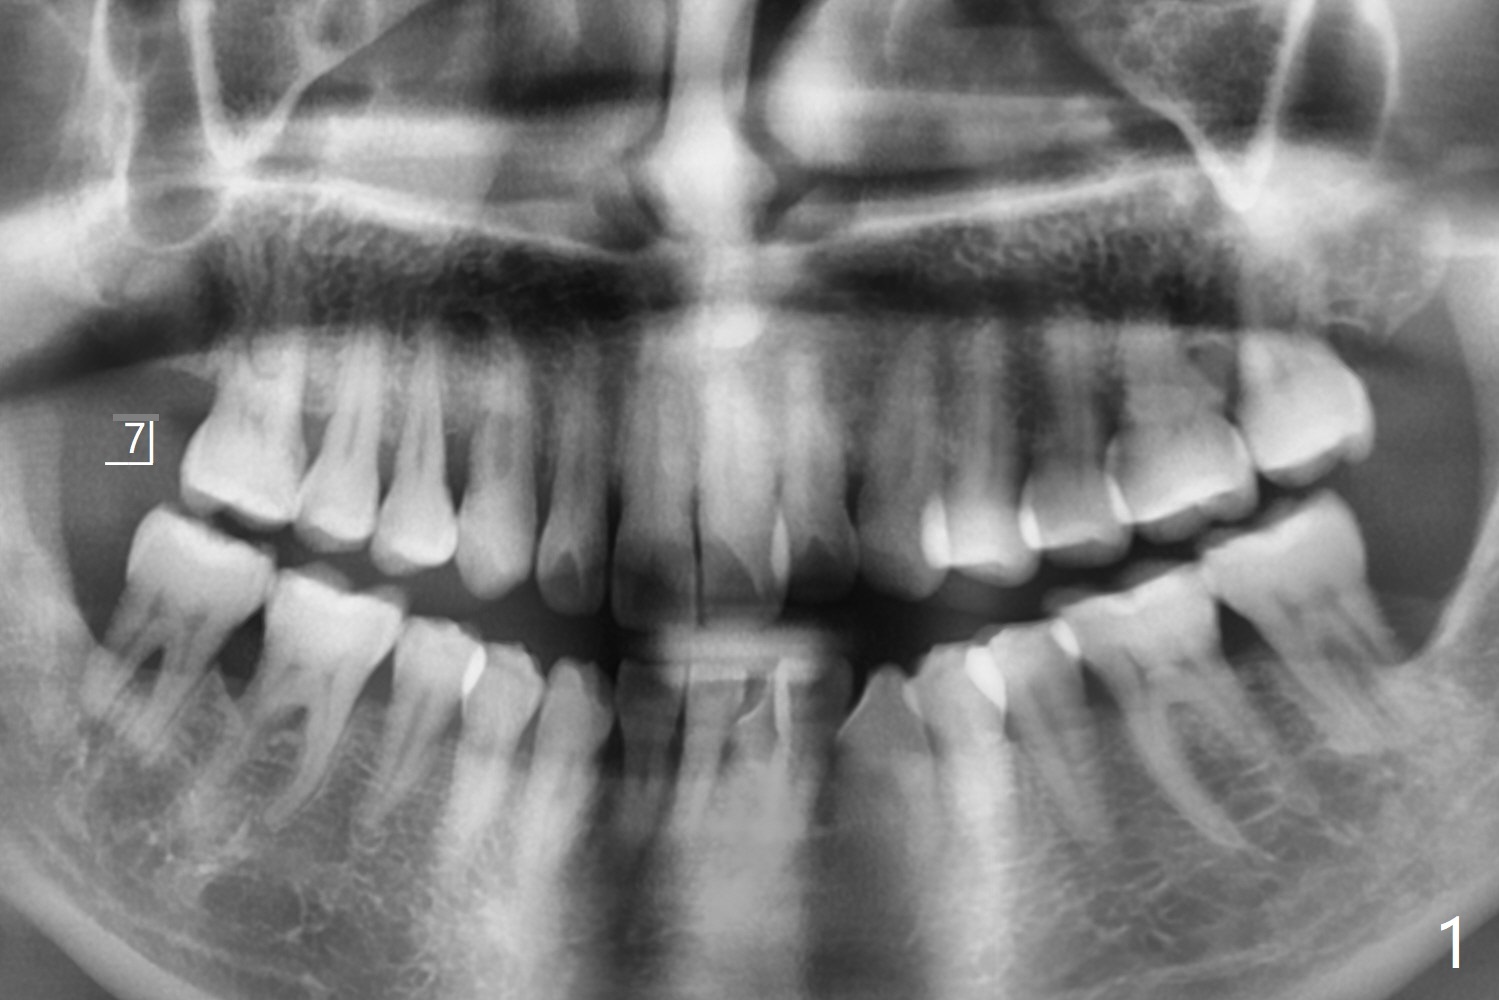

53岁男一年前在别的诊所做右上7拔牙植骨,现在要求植牙(图一),其余牙齿骨质吸收严重,植牙更显得重要。缺牙区植骨密度正常,但是牙槽嵴不平(图二:箭头),导板种植,植体可能偏向低处(阻力低的区域:远中,腭侧(图三:箭头)),几年后可能出现螺纹暴露